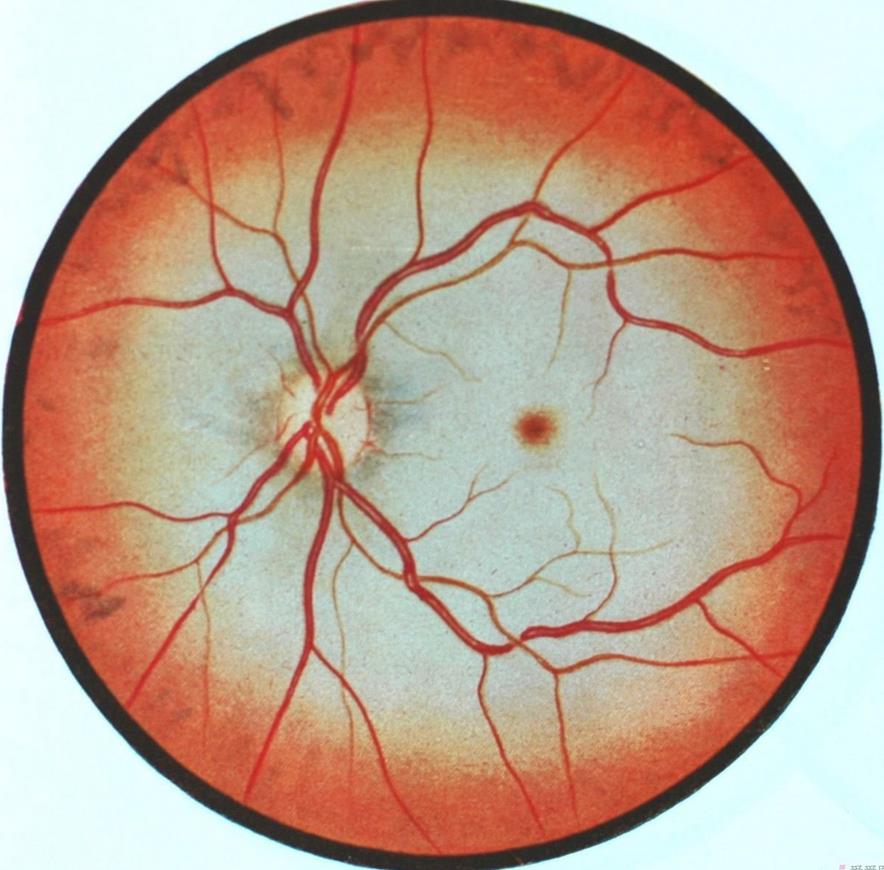

-

盲点:下图中,血管汇集处的高亮区域即为盲点